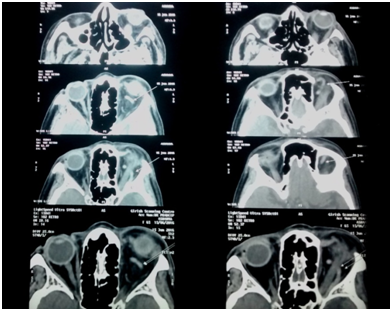

Blood counts and investigations were as follows: Hb 11.6 g%, total count 9300 with neutrophil 58.4%, lymphocytes 29%, random sugar levels were fluctuating, Blood urea 19, serum creatinine 0.69. Prothrombin time of 11.3s and INR 1.01.Mantoux test was negative for tuberculosis. Nasal swabs and culture ruled out bacterial and fungal sinusitis. Thyroid profile was within normal limits, Anti neutrophil cytoplasmic antibody (ANCA) was negative, and Angiotensin converting enzyme (ACE) levels were within the normal range, hence we were able to rule out thyroid orbitopathy, sarcoidosis and wegeners granulomatosis. CT orbit showed left eye proptosis with minimal fat stranding and superior ophthalmic vein enlargement. MRI confirmed a left dilated and engorged SOV, suggestive of SOV thrombosis, congested extraocular muscles and features suggestive of compressive optic neuropathy (Figure 4). The MRI also identified an acute ischemic infarct with haemorrhagic transformation in the left lateral aspect of pons in the brain.

Figure 4 MRI showing dilated and tortuous superior ophthalmic vein in multiple sections (white thin arrows).